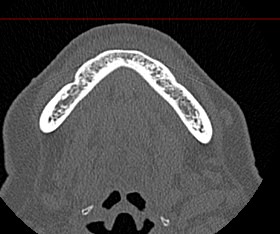

Мультиспиральная компьютерная томография челюстно-лицевой области относится к лучевым методам исследования и включает в себя сканирование верхней и нижней челюстей, зубов, височно-нижнечелюстных суставов, мягкотканных структур ротовой полости. Преимуществами КТ является быстрота, безболезненность и неинвазивность (то есть исследование не требует вмешательства в организм).

В результате сканирования получается серия изображений, которые отображают состояние челюстно-лицевой зоны, особенности анатомического строения и позволяют выявить воспалительные изменения, травматические повреждения, опухолевые образования, аномалии развития. Проявления артроза височно-нижнечелюстных суставов могут создавать неприятные ощущения при жевании. Также зачастую воспалительные изменения придаточных пазух носа связаны с пролабированием зубов верхней челюсти в область альвеолярных бухт верхнечелюстных синусов.

В наших медицинских центрах обследование челюстно-лицевой зоны проводится на современных мультиспиральных компьютерных томографах экспертного класса TOSHIBA AQUILION. 64- и 128-срезовый компьютерные томографы послойно сканируют исследуемую область с шагом от 0,5 мм, получая детальные изображения высокого уровня четкости и контрастности.

С помощью цифровой обработки данных проводится объемная реконструкция и построение 3D-изображений челюстно-лицевой области, что дает возможность визуализировать пространственное соотношение анатомических структур и повышает точность диагностики. При этом возможности аппаратов обеспечивают пониженный уровень дозы облучения для организма человека.